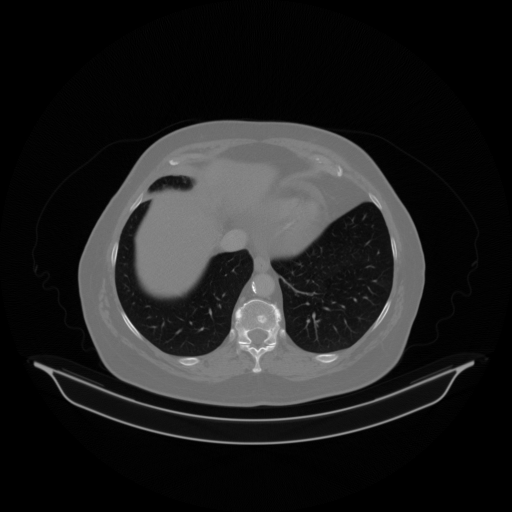

Original VENOUS CT scan

Full window (WL 1023.5, WW 4095 β†’ Low βˆ’1024, High +3071)

Actual HU range: [-1024.0, 1092.0]

Lung window (WL -600, WW 1500 β†’ Low βˆ’1350, High +150)

Actual HU range: [-1024.0, 150.0]

Mediastinum window (WL 40, WW 400 β†’ Low βˆ’160, High +240)

Actual HU range: [-160.0, 240.0]